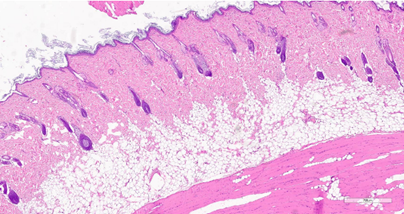

При проведении гистологического исследования образцов, полученных у особей из группы 2, можно проследить наличие очагового истончения эпидермиса и фиброза (рис.8) при выраженном уменьшении количества сально-волосяных комплексов (рис.9). Вместе с тем у одной из особей группы2 можно наблюдать отсутствие морфологических изменений в дерме, которые могли бы указывать на эффект энергетического воздействия (рис.10).

Рис. 8. Очаговое истончение эпидермиса и очаговый фиброз поверхностного слоя дермы на 47-й день после процедуры воздействия RF-микроиглами.

Окрашивание гематоксилином и эозином (х400).

Примечание: рисунок составлен авторами по результатам данного исследования